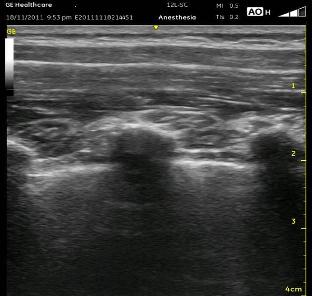

Once I have determined the sites for injection or injections, I start several centimeters laterally in a paramedian plane and follow the ribs medially. After identifying the bright shimmering white comet-tail appearance of the pleura moving with inspirations, watch for the rounded ribs to become more squared and shift slightly cranially. This is the transition from the rib to the transverse process. It can be a very subtle change. If you travel too far medially, the separated squared lines of the transverse process will become one jagged line representing the facet joints and laminae. In the series of images below (ribs, transverse processes then facet joints), the erector spinae muscles can be seen above the two layers of intercostal muscles. Cranial is to the right, and you can tell by the widening of the paravertebral space as you look from left to right.

Once you are appropriately over the transverse processes, angle the probe slightly medially (so that the beam is ‘looking’ laterally). This will allow the Superior Costotransverse Ligament (SCTL) to optimally (or at all) come into view. It is the bright white line just above the pleura in the images above. This is the critical element to recognize. This oblique maneuver is necessary to orient the probe to the ligament at a 90 degree angle because of the rounded nature of the ribs which are diving anterior (deep) as they approach each other at their posterior aspect at the spine. To see it at the most perpendicular angle, you must position the probe obliquely. As mentioned above, the SCTL will be seen going from deep to superficial as it goes caudal to cranial. That is because it attaches between the superficial aspect of the rib and the deep aspect of the transverse process cranial to it. Your goal is to put the needle just deep to the SCTL in the wedge-shaped darkened space just superficial to the pleura.